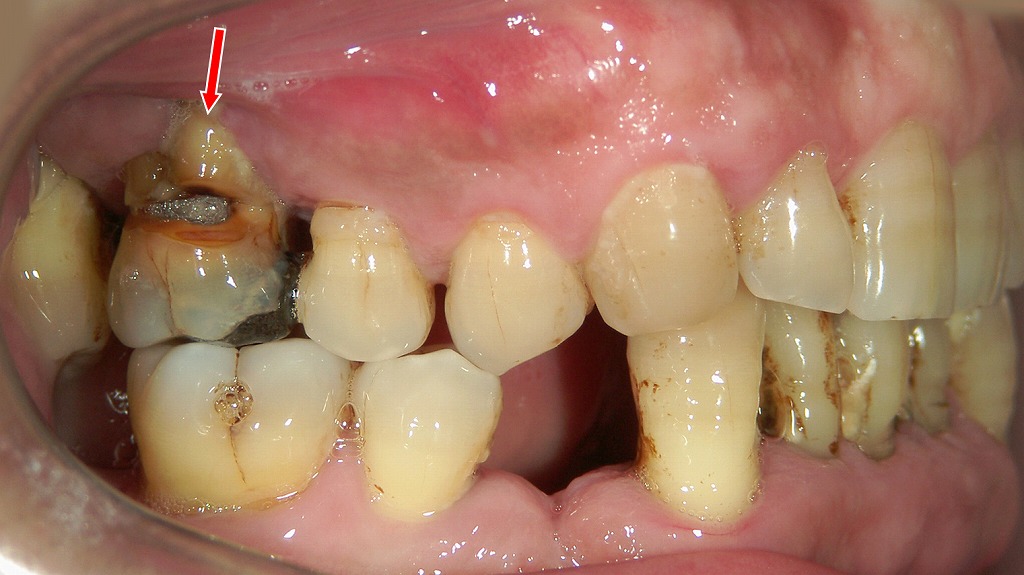

赤矢印の親知らず周囲で炎症が起き、歯茎の腫れや膿の排出につながる「智歯周囲炎」の典型例です。親知らずが斜めに埋まっていることで清掃が難しく、細菌が繁殖して膿が溜まりやすい状態になっています。

1. 歯周病により歯周ポケットから排膿している症例

この画像は、右下5番(下顎の第一小臼歯)の歯頚部から膿が排出している様子を示しています。

赤い矢印の指す部分に、歯と歯ぐきの境目(歯頚部)から白っぽい膿が確認できます。

このような状態は、**歯周組織の感染(歯周膿瘍)**によって起こることが多く、歯肉の深部に細菌感染が生じ、炎症性の膿が歯肉縁から排出されています。

🔍 推定される原因

- 進行した歯周病(歯周ポケット内感染)

プラークや歯石によって歯根面に炎症が広がり、歯周ポケット内に膿がたまる。 - 深い歯周ポケットの形成

ポケット内に酸素の少ない環境が生じ、嫌気性菌が増殖して膿を生じる。 - 噛み合わせや清掃不良による悪化

金属冠の縁や歯石の残存が感染の温床となっている可能性が高い。